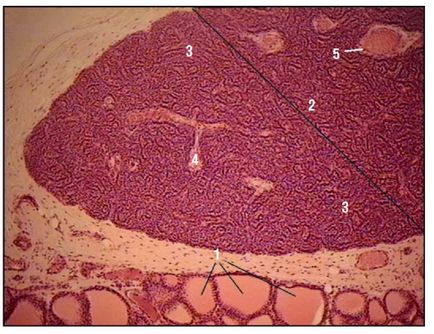

Fig. 168. Glanda tiroidă. Lobule (colorare cu hematoxilină și eozină, creștere mică): 1 - glandă lobulară: 2 - folicul; 3 - coloid în cavitatea foliculului; 4 - epiteliul interfollicular; 5 - țesutul conjunctiv interlobular; 6 - vasele de sânge; 7 - celulele grase